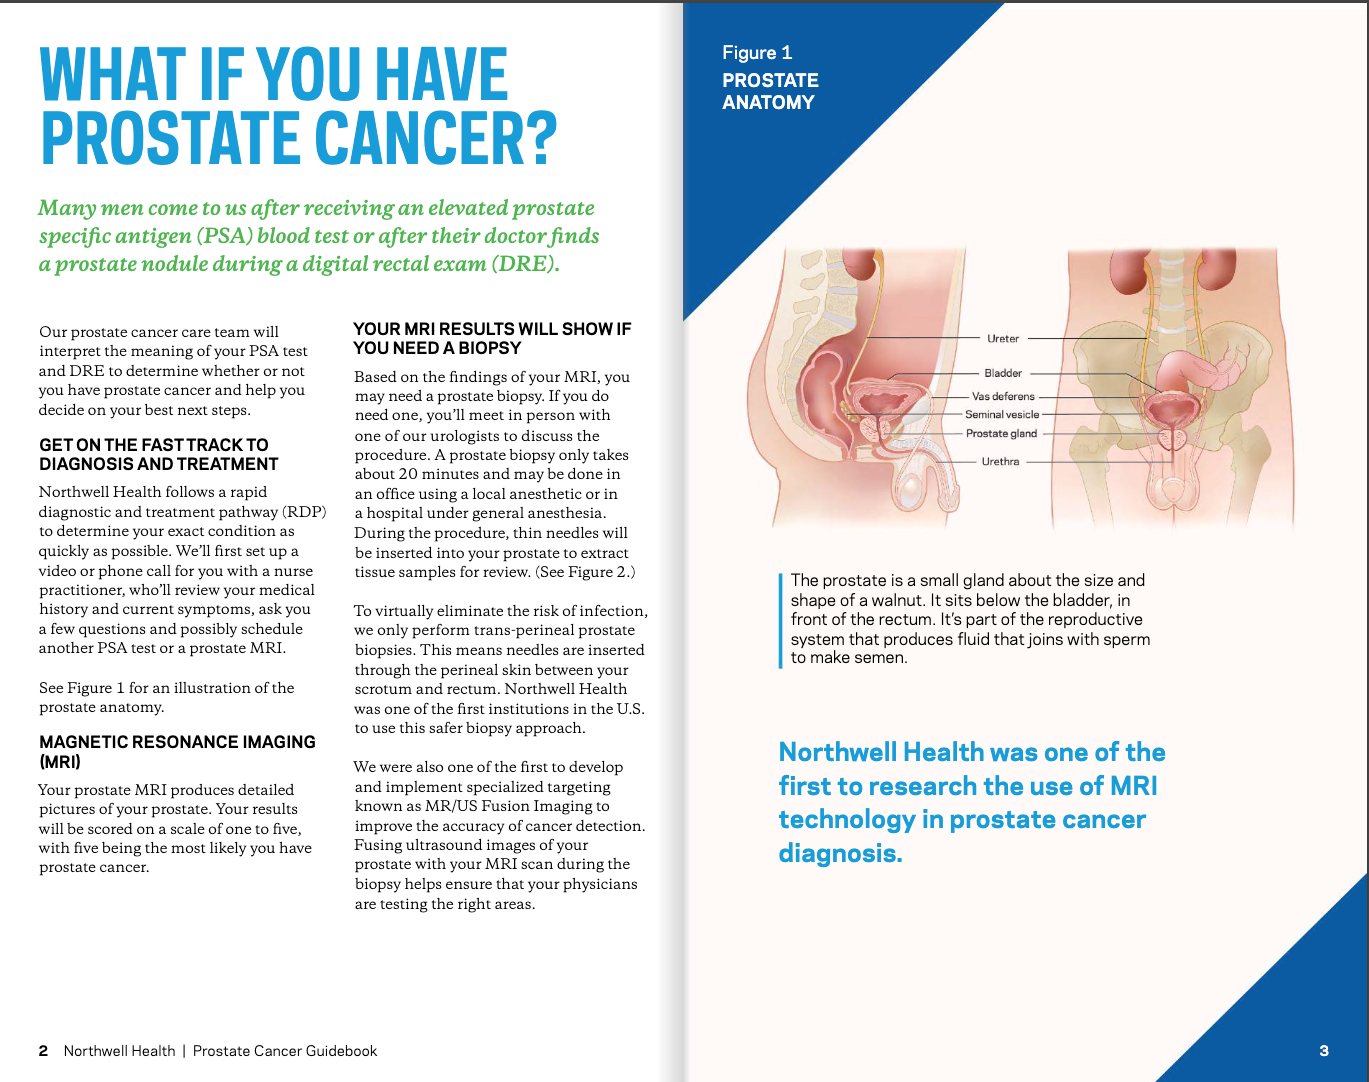

Prostate Cancer Booklet

Created clear, accurate, and visually engaging medical illustrations for a patient education booklet on prostate cancer for a hospital system. The illustrations simplified complex anatomical and clinical concepts, helping patients better understand diagnosis, treatment options, and disease progression.

Client: Northwell Hospital System

Patient Education: Prostate Cancer